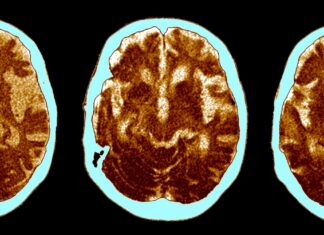

The curious link between Alzheimer’s disease and cancer

In recent years, scientists have been starting to ask themselves this question: What if Alzheimer's disease isn’t simply a disease of the brain? It certainly has always seemed to be. The defining feature of Alzheimer's—the most common form of dementia, affecting millions of people worldwide—is the buildup of proteins that cause amyloid plaques and tau tangles in